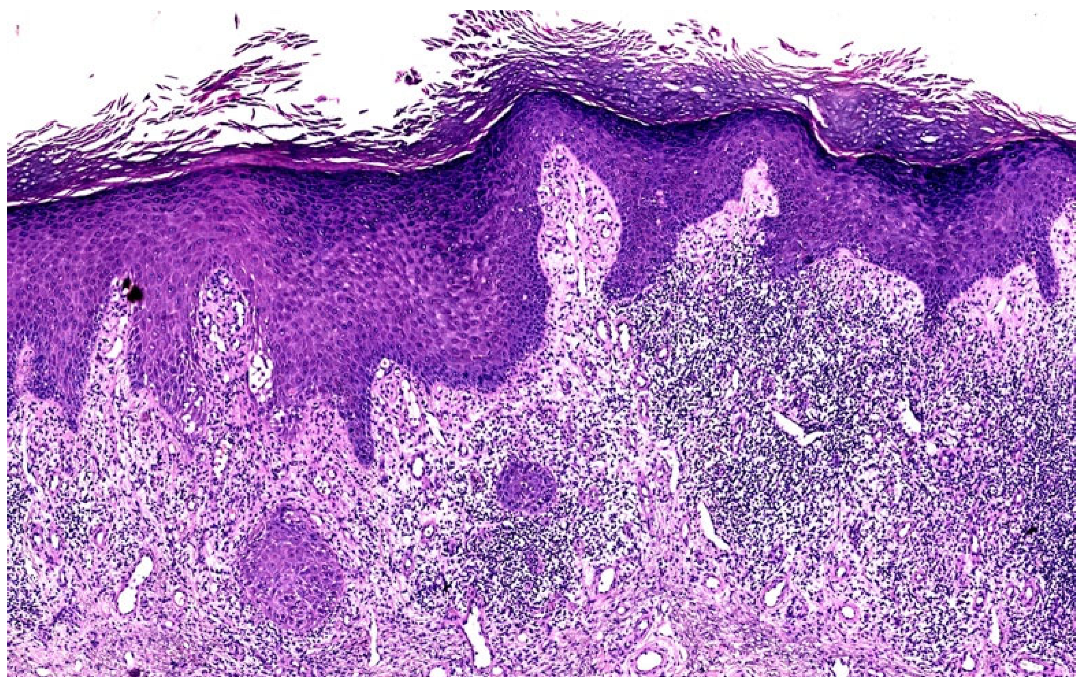

3.2.1. Hypertrophic Lichen Planus (HLP)

| HLP | Thickened, verrucous, purple-red, plaque/nodule | Wedge-shaped | Pseudoepitheliomatous hyperplasia, endophytic well-differentiated squamous epithelium extending not beyond the superficial dermis | Irregular | Present | Basal cell vacuolar alteration; thickening of collagen fibres in the papillary dermis | Longer mean duration and often unremitting compared with LP |